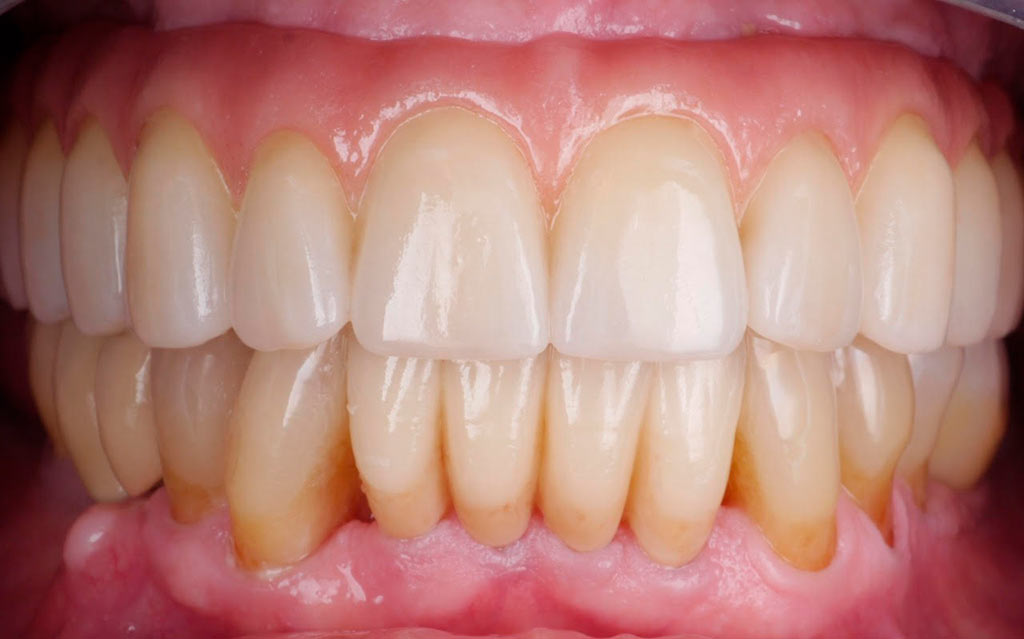

Completa inmediata,cirugía guiada, prótesis, puente de zirconio

Rehabilitacion de paciente con destrucción dental